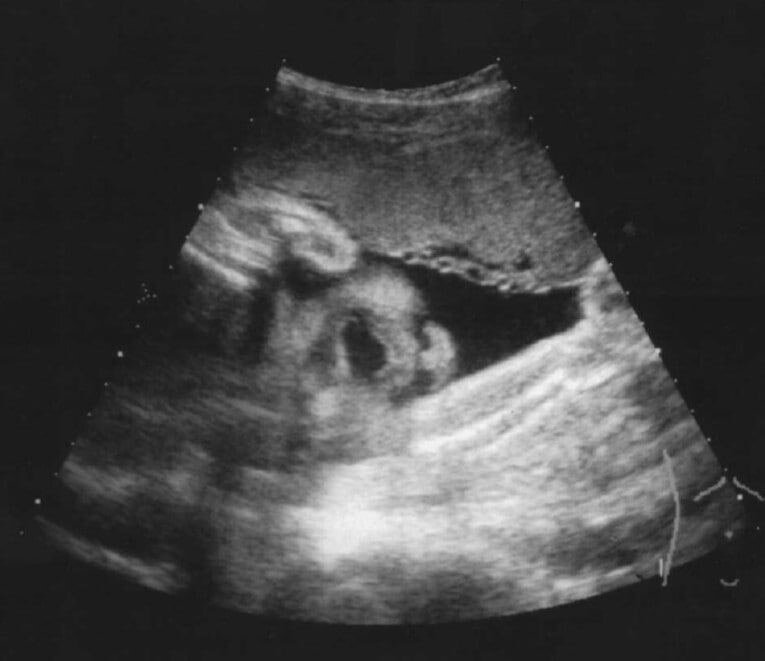

Одним из важнейших демографических показателей является младенческая смертность. Рассчитывается следующим образом: нужно поделить число умерших детей на первом году жизни за год на число детей, родившихся живыми за этот же год и умножить на 1000.

Этот показатель важен, так как он показывает качество оказываемой медицинской помощи, уровень здоровья населения и прочие показатели, которая влияет на здоровье детей. Изменение младенческой смертности говорит о правильной или неправильной политике, проводимой государством. Знаю, звучит очень заумно, пафосно и официально, но так нам говорили в универе.

Простым языком: смертность детей на первом году жизни, зависит не только от самих детей и матерей, но их от медицинских, социальных и экономических условий.

Для примера в 1950 году показатель составлял приблизительно 88 ребенка на 1000 родившихся, а в 2010 всего 7,5.

На момент ноября 2020 года младенческая смертность снизилась на 60 детей по сравнению с ноябрём прошлого года. В общей сложности за 11 месяцев показатель снизился на 13,1% по сравнению в 2019. Сейчас он составляет 4,4 ребенка на 1000 родившихся. Если не ошибаюсь, этого планировали достичь к 2023 году.